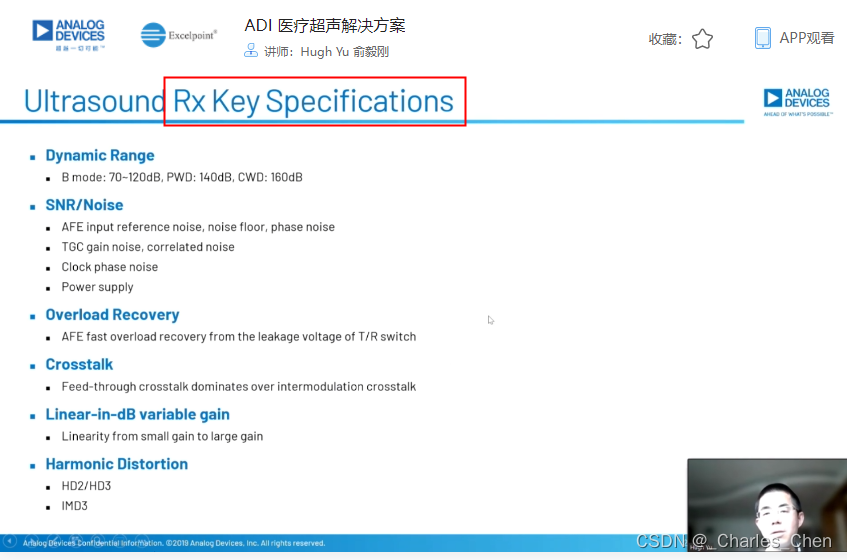

成像通道接收机

超声成像通道的接收机用于检测二维(2D)信号以及彩超流体成像所需的脉冲多普勒(PWD)信号和频谱PWD。接收机包括Tx/Rx开关、低噪声放大器(LNA)、可变增益放大器(VGA)、抗混叠滤波器(AAF)和模/数转换器(ADC)。

VGA有时也称为时间增益控制(TGC)放大器,能够在整个接收周期内为接收机提供足够的动态范围。超声信号在体内大约每秒传输1540米,往返衰减率为1.4dB/cm-MHz。发射一个超声脉冲后,可立即在LNA输入接收到高达0.5VP-P的回波信号,该信号会快速跌落到传感器单元的热噪声基底。接收该信号所要求的动态范围约为100dB至110dB,超出了实际ADC的输入量程。因此,需要利用VGA 将信号转换成与ADC量程相当的信号幅度。典型应用中采用12位ADC,要求VGA能够提供30dB至40dB的增益。增益随时间调整(即“时间增益控制”),实现所要求的动态范围。

超声接收机的瞬态动态范围也很关键,它会影响2D图像的质量和系统检测多普勒偏移(血液或组织的运动)的能力,尤其是在二次谐波成像系统中,感兴趣的二次谐波信号明显低于发射信号的基波。对于小的多普勒信号同样如此,多普勒信号频率可能在1kHz以内,幅度远远低于组织或血管壁的反射信号。因此,需要特别关注可变增益放大器的带宽和近载波SNR,这些参数通常是制约接收机性能的关键。